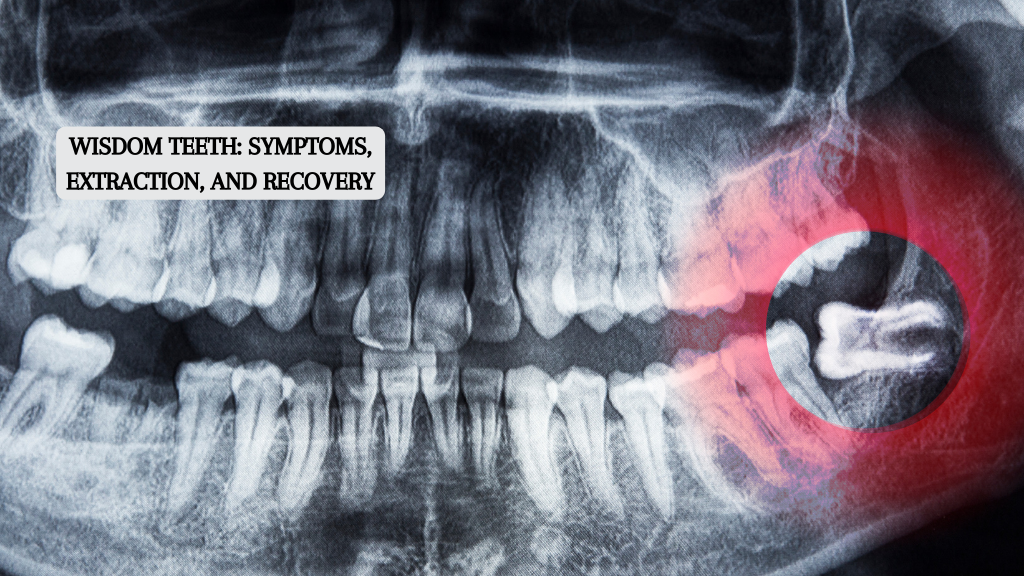

The wisdom teeth, often called third molars, are the last set of teeth that erupt from your mouth’s back corners. While in good condition and alignment, they can be a great help, but they frequently produce issues that necessitate their removal. This article...